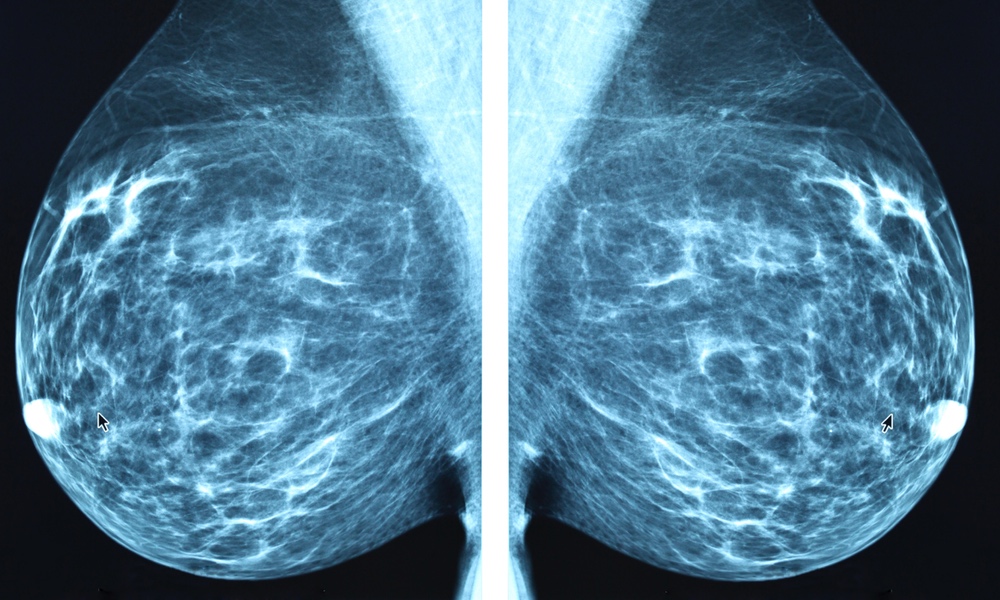

Data from almost 55,000 women 70 years old and older in the SEER (Surveillance, Epidemiology, and End Results)-Medicare registry were included in the current analysis. The women were divided into three groups: ages 70 to 74, 75 to 84 and 85 and older. All participants had a screening mammogram in 2002, and were followed for up to 15 years. Those who did not undergo another screening mammogram within three years of their 2002 mammogram served as the control group.

Among women ages 70 to 74 who continued screening, an estimated 31 percent of breast cancers were overdiagnosed; in women ages 75 to 84, about 47 percent were overdiagnosed; and among women 84 and older, about 54 percent of cancers were overdiagnosed.

The technologies used for mammography in this study were older technologies. Today, 3D mammography is used almost exclusively. While it is better at detecting breast cancers, it may actually contribute to overdiagnosis among older women. “Questions about how modern screening approaches may or may not contribute to overdiagnosis are important to think about,” Richman said.